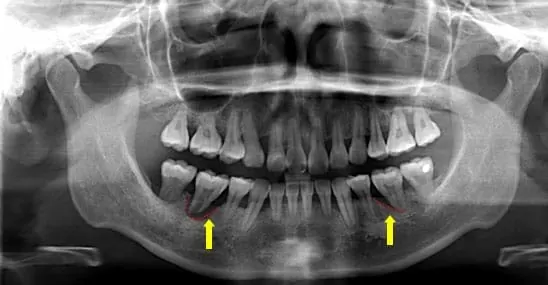

圖 2: 三年後再次牙周病診斷的X光片

說明:患者的牙周病拖延3年未曾治療,X光片顯示出患者牙牙齒齒槽骨已遭受嚴重侵蝕,齒槽骨的骨頭高度明顯比三年前降低許多(如箭頭所示),牙根的地基喪失,牙齒致使搖動不穩無法咬合。